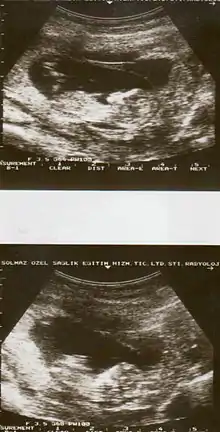

| Diagnostic method | Based on symptoms, ultrasound[1] |

The cause of placental abruption is not entirely clear.[2] Risk factors include smoking, pre-eclampsia, prior abruption (most important and predictive risk factor), trauma during pregnancy, cocaine use, and previous cesarean section.[2][1] Diagnosis is based on symptoms and supported by ultrasound.[1] It is classified as a complication of pregnancy.[1]

Placental abruption is suspected when a pregnant mother has sudden localized abdominal pain with or without bleeding. The fundus may be monitored because a rising fundus can indicate bleeding. An ultrasound may be used to rule out placenta praevia but is not diagnostic for abruption.[8] The diagnosis is one of exclusion, meaning other possible sources of vaginal bleeding or abdominal pain have to be ruled out in order to diagnose placental abruption.[5] Of note, use of magnetic resonance imaging has been found to be highly sensitive in depicting placental abruption, and may be considered if no ultrasound evidence of placental abruption is present, especially if the diagnosis of placental abruption would change management.[16]